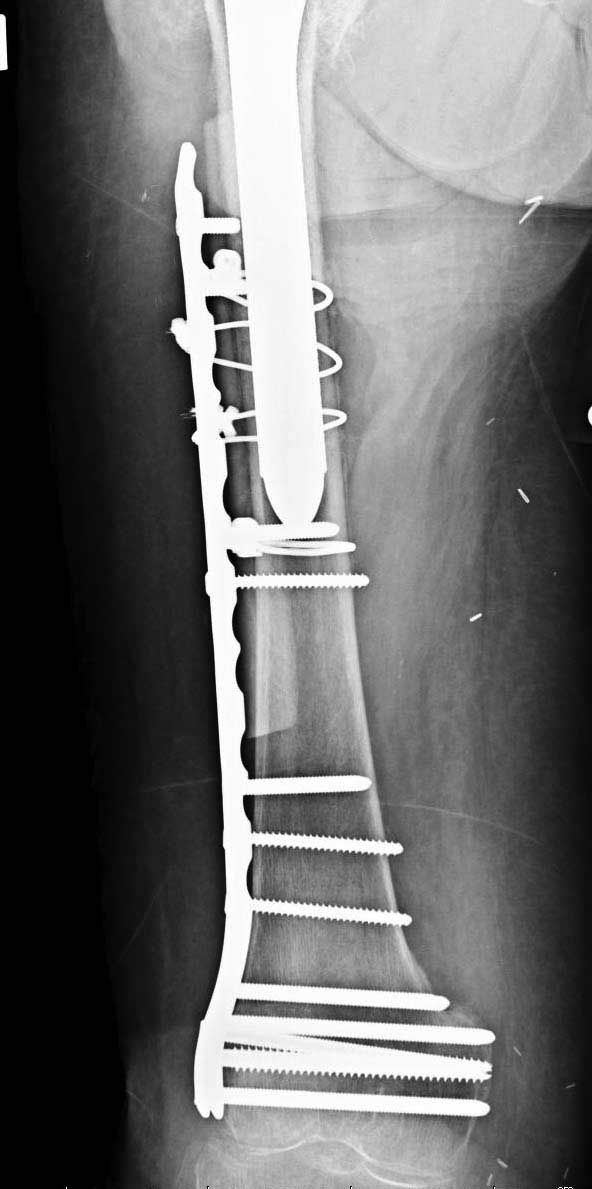

Обычно после чрезвертельных переломов, за исключением молодых, у пожилых остается нестабильность при движении. Часто падают и после 3х мес. в результате падения обнаружен перипротезный перелом (22-23), который зафиксирован Синтез пластиной.